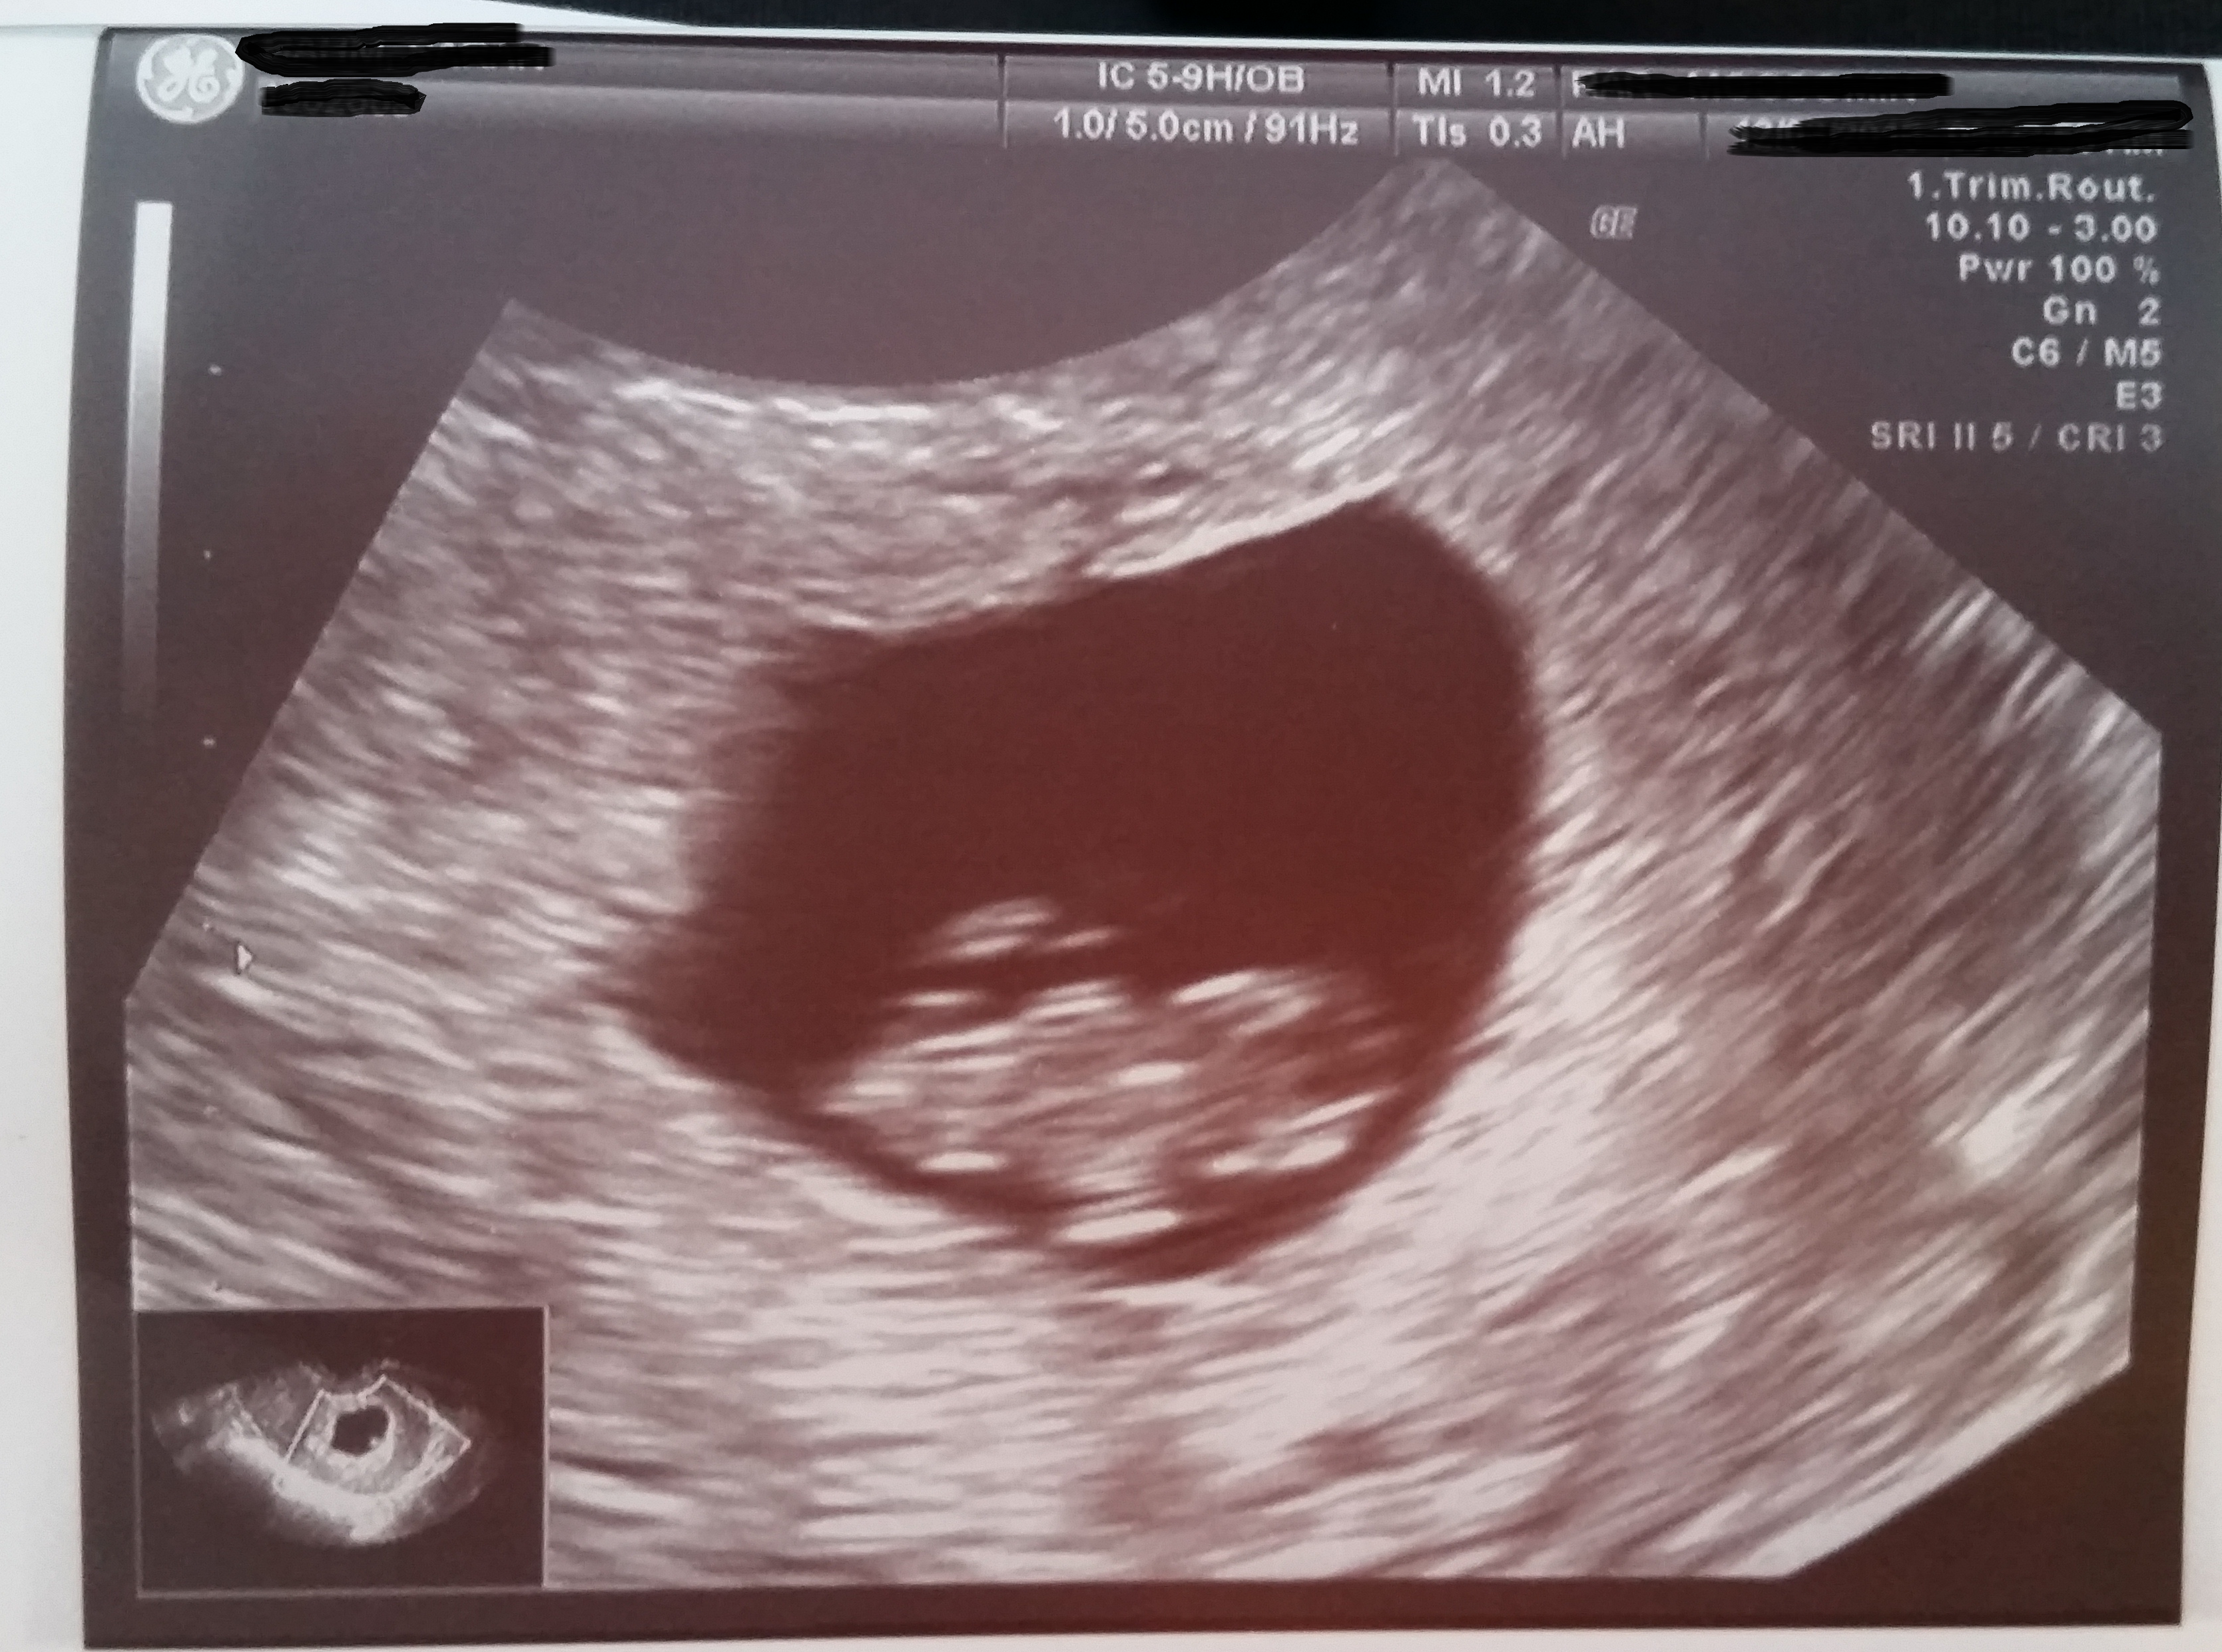

Baby has grown so much!!! It's no longer a little peanut like when we saw it for the first time at 6w3d. Today at 10w3d he/she was waving and kicking the feet around, heartbeat of 160 something. My heart is bursting with love for this precious little life.

Here's our nugget at 10w!!! So happy to see he/she moving around and the little heartbeat at 160BPM (Sorry had an error with the above post not sure how to delete it)